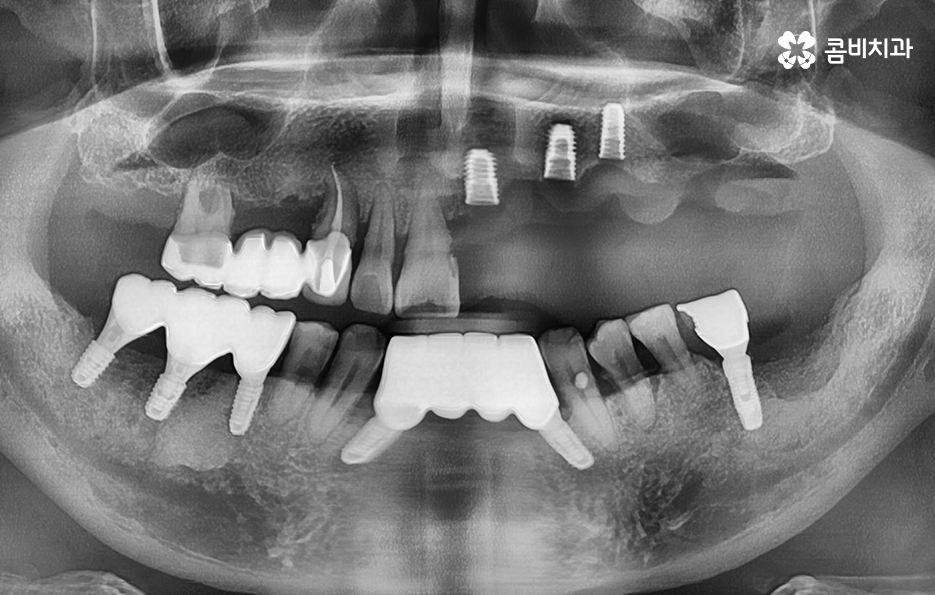

위 환자분의 케이스는 치주염이 심해져서 치아를 잃게 되기도 했지만 윗니의 경우 브릿지로 치아 기능을 유지하다가 결국 임플란트를 하게 된 사례로 볼 수 있어요

과거에는 임플란트 치료 자체가 없어서 브릿지나 틀니와 같은 치료를 할 수 밖에 없었지만 브릿지와 틀니의 한계점은 치아의 기능적인 부분에서도 한계점이 분명하지만 그에 더해 치조골이 점점 내려 앉고 흡수된다는 점에서도 임플란트의 장점이 명확하다고 할 거예요